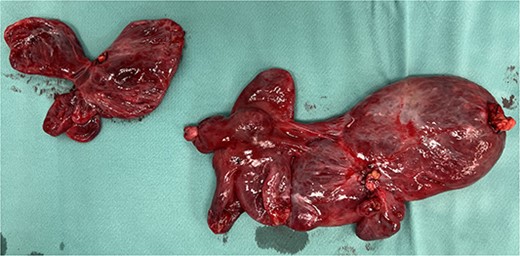

A 59-year-old woman presented to the abdominal surgery unit of our hospital for a dimensional increase of known epigastric multiloculated cystic formation detected on computed tomography (CT)-scan follow-up, with a maximum diameter of~20 cm (Fig. 1). Her medical history included breast and colon adenocarcinoma and scapular melanoma, all of which were surgically treated in addition to chemo, hormone and radiation therapies. The patient was asymptomatic. Blood tests were unremarkable. At explorative laparotomy, a voluminous multi-chambered and well-vascularized cystic formation was found (Fig. 2). Surgical excision was performed after ligation of the two vascular peduncles located in the small omentum (Fig. 3). Histological findings showed an angioleiomuscular tumor with cavernous aspects and uncertain potential for malignancy. The patient was discharged on postoperative day 4 without complications. At follow-up visits at 1, 3 and 6 months, the patient was in good condition with no disease recurrence.

Surgical piece illustrating the two vascular pedicles of the neoformation.